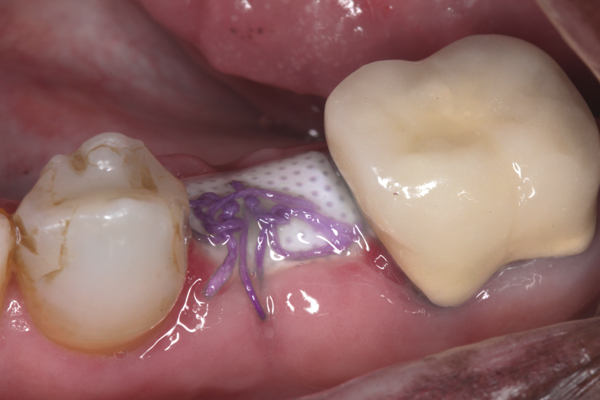

Fig 17. Bone graft was placed in the socket and a d-PTFE barrier was used to cover the graft. The bone graft material was placed beyond the alveolar housing to accommodate shrinkage of graft material and to facilitate attaining a wide alveolar ridge. The barrier was removed after 6 weeks.

Figure 17

Fig 18. Healed ridge exposed after 6 months.

Figure 18